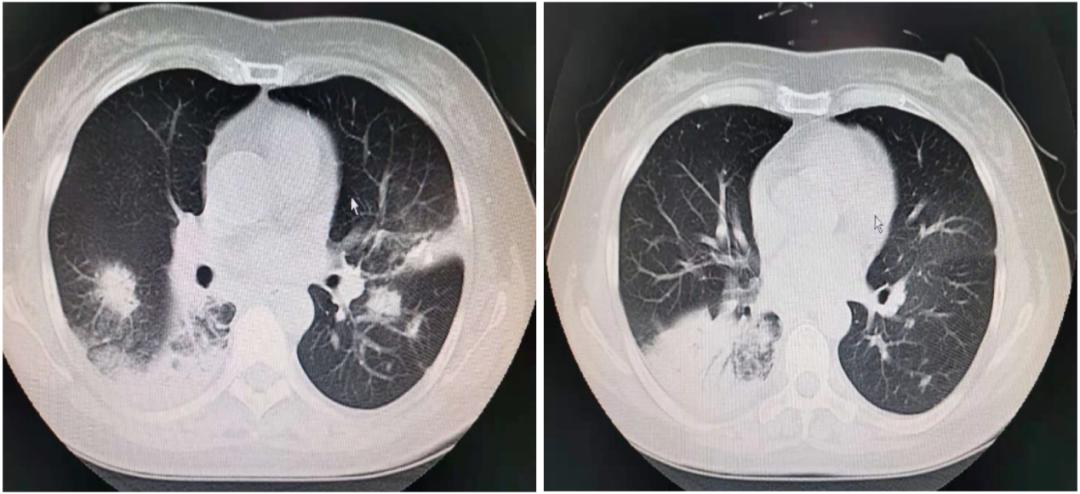

2020年10月30日胸部CT示:双肺见多发斑片状高密度影,边界模糊,其内可见充气支气管影,部分其内见结节状钙质密度影,余肺野清晰。纵隔内见肿大淋巴结(图1)。

图1:胸部CT提示双肺多发高密度影,边界模糊,其内见充气支气管影